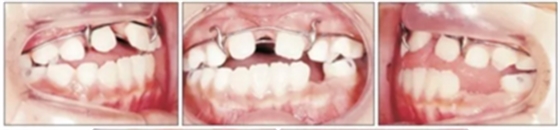

第二階段(圖5,6;表2)

面弓矯治包括在混合牙列及早期恒牙列的傳統(tǒng)牙支抗面弓及恒牙列的骨支抗面弓。由于患者曾行腭成形術(shù),為了將矯治力傳遞到上頜骨,使用唇舌弓而不是快擴(kuò)。8歲5月時開始用面弓聯(lián)合唇舌弓矯治(500g/邊,與合平面呈30°向下),持續(xù)3年6月。患者佩戴時間為12-14時/天。